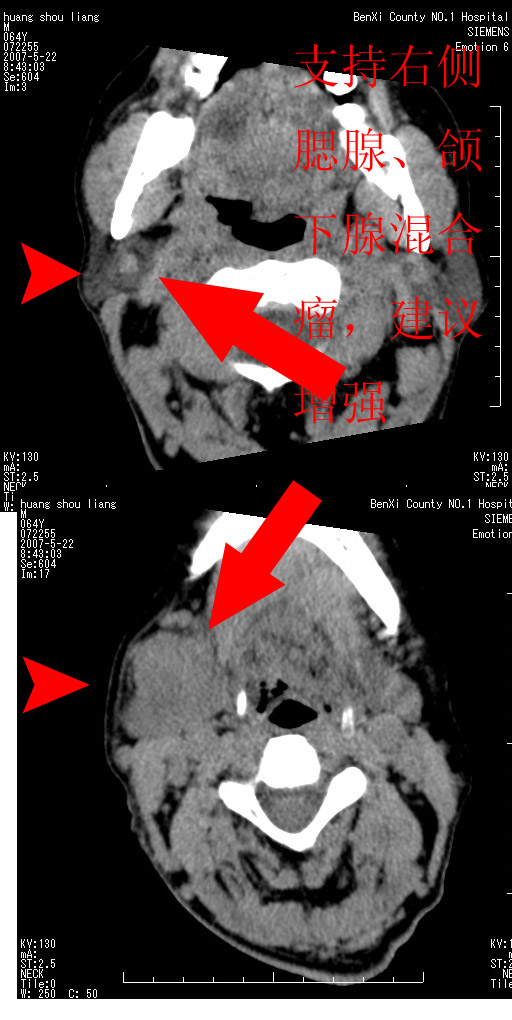

考虑来源于右侧腮腺及颌下腺的混合瘤

对不起大家,可能是片子发太多有点乱,正常腮腺在下颌角的外侧,颌下腺在下颌体的中部内侧,本例在下颌角内侧偏下,和腺体一点关系都没有,从vrt和mpr上可以很明显看出来,再者肿块是好多粘连在一块的,大家在仔细看看,左侧可能也是吧,我还是考虑为肿大的淋巴结融合在一块,但性质??????

右侧腮腺下部均匀软组织密度肿块,外形不规则,与周围组织分界清晰,考虑右侧腮腺混合瘤或多形性腺瘤。

大家好,病理结果出来了,如大家所说,颌下腺混合瘤。

唉,解剖没学好吧,我诊断错了,不过还是有些不理解回去我在多看看书,谢谢大家的参与,以后我还会奉献好的病例。